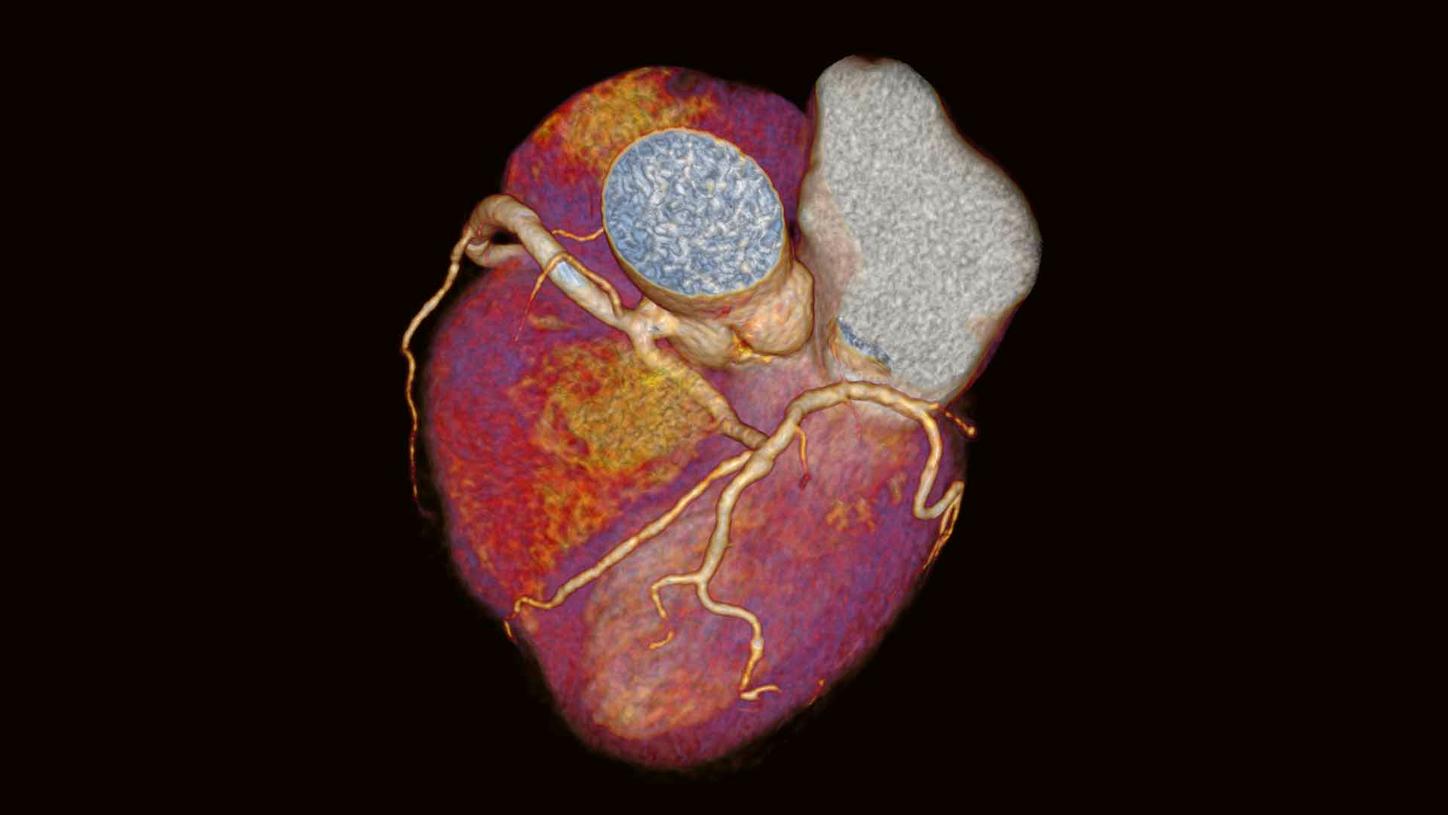

Application Training for Computed TomographyCourse overview - explore our offerings

These courses are offered as classroom training in our Training Centers or as as virtual classroom training independently where you are located. Theoretical principles of imaging are supplemented by a wide range of practical exercises, giving you the opportunity to gain skills for day-to-day clinical work. In our virtual courses we impact practical knowledge in clear, manageable units and focus on retaining the interactive approach that you are familiar with from our face-to-face training. Learn in the virtual work space and benefit from innovative digital methods.